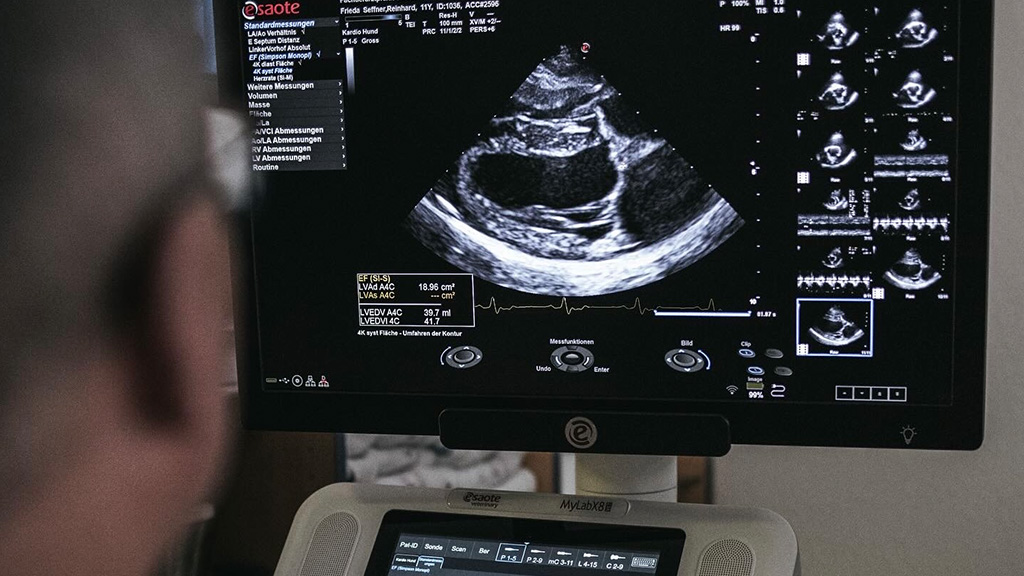

In unserer Praxis besteht die Möglichkeit von den verschiedensten Organen eine sonografische Untersuchung durchzuführen, wie z.B. Trächtigkeitsuntersuchungen, Herzuntersuchungen oder Ultraschalluntersuchungen anderer innerer Organe (Verdauungsorgane, harnableitende Organe, Leber, Geschlechtsorgane, Nebenniere etc.).

Die Indikationen für eine Ultraschalluntersuchung sind insbesondere in der Kardiologie und in der Gynäkologie neben anderen Untersuchungen fast immer angezeigt. Denn im Gegensatz zum Röntgen kann hier auch eine Aussage über die Funktion des Herzen gemacht werden. Auch können kleinste Details, auch im Inneren der Organe, genau dargestellt und vermessen werden.